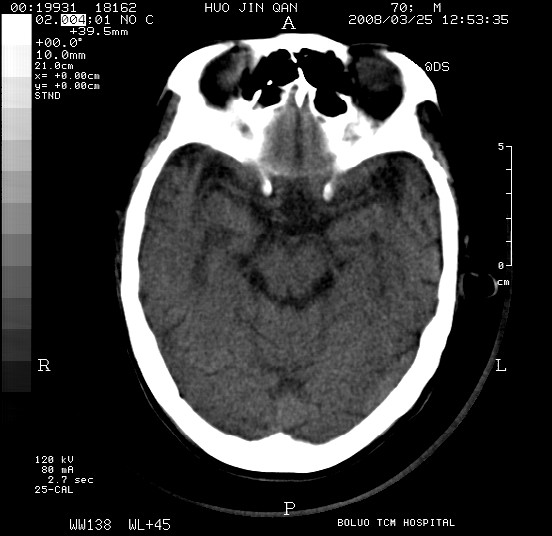

以下是引用随光逐影在2008-3-25 20:15:00的发言:[br]双侧额颞顶部亚急性(或慢性)硬膜下血肿。

以下是引用liuyue在2008-3-26 18:57:00的发言:[br]以下是引用随光逐影在2008-3-25 20:15:00的发言:[br]双侧额颞顶部亚急性(或慢性)硬膜下血肿。 [br]支持![br]可以无明显外伤病史,老年人可以在激烈摇晃或轻微头部碰创头部时,发生硬膜下出血.